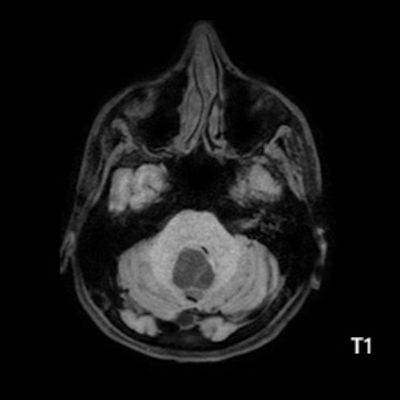

- A) Beyin BT incelemede; posterior fossada hipodens, düzgün sınırlı kistle beraber (oklar), posteriorunda 8 mm boyutunda, iyi sınırlı, kontrastsız BT’de parankim ile izodens, postkontrast görüntülerde yoğun kontrast tutulumu gösteren mural nodül komponenti (oklar) gözlenmektedir.

- B) Beyin MRG incelemesinde; 4. ventriküle bası etkisi oluşturan yaklaşık 3.5 cm boyutta, T2A hiperintens T1A hipointens kistik komponent (oklar) ve posteriorunda T1 ve T2A serilerde parankim ile izointens, içerisinde flow void alanların (oklar) izlendiği, post kontrast görüntülerde yoğun kontrast tutulumu gösteren mural nodül (oklar) barındıran düzgün sınırlı lezyon izlenmektedir.

- Kistik komponent: T1A hipointens, T2A hiperintens

- Mural nodül: T1A izo-hipointens, T2A orta derecede hiperintens olabilir.

- Kontrastlı incelemelerde mural nodül belirgin ve yoğun kontrast tutulumu gösterir. Ancak kist duvarında genellikle kontrastlanma beklenmez.

- T1 ve T2A görüntülerde flow voidler sıktır.